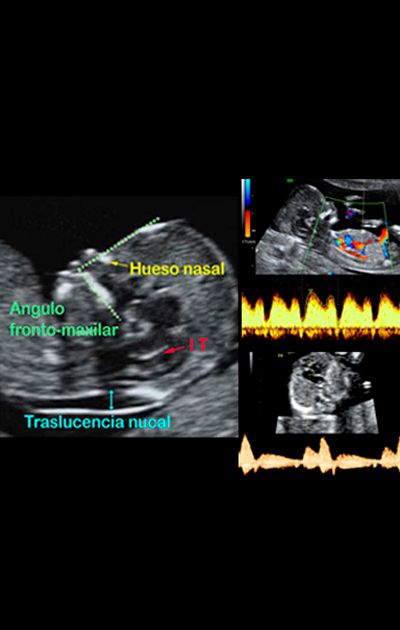

ExamesUltrasom 2D | 3D e 4DUltrassom Doppler ColoridoEcocardiografía FetalCálculo de risco S.Down.